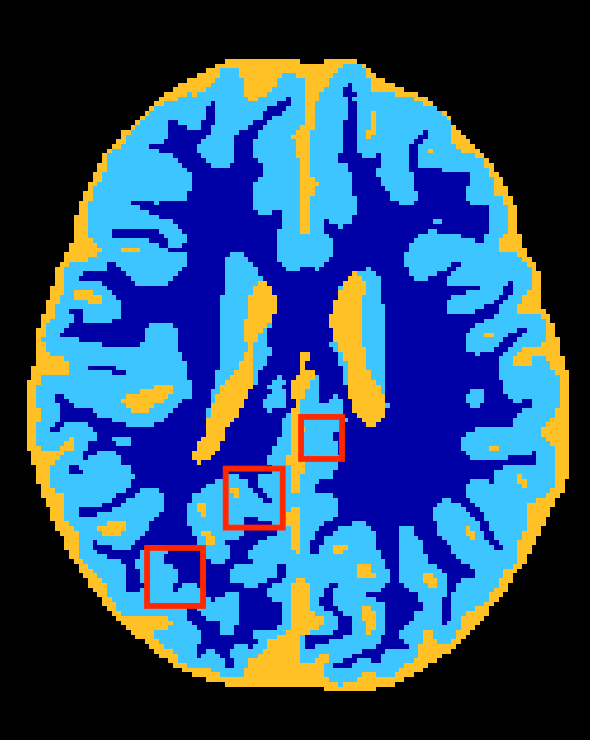

Figure 3 depicts visual results for the subject used in validation. It can be observed that HyperDenseNet (middle) recovers thin regions better than the baseline (left), which can explain improvements in distance-based metrics. As confirmed in Table 2, this effect is most prominent in boundaries between the gray and white matter. Further, HyperDenseNet produces fewer false positives for WM than the baseline, which tends to over-estimate the segmentation in this region.

Baseline

HyperDenseNet

Reference Contour